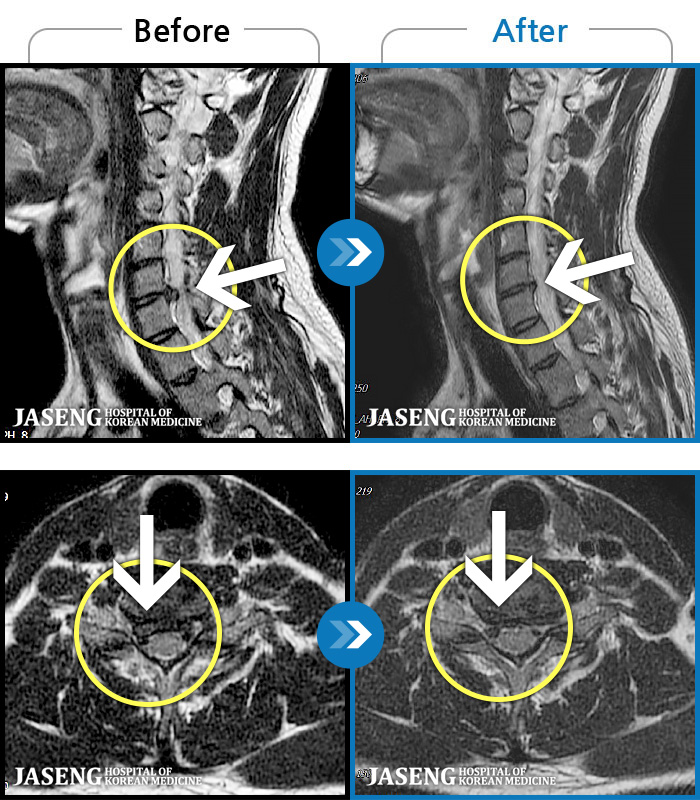

목디스크

인천 · 조남훈 원장

증상이 재발하였습니다.

촬영시기

2021.11.20 ~ 2025.11.13

2025.11.21